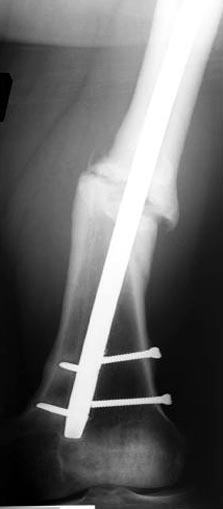

Из истории болезни: два года назад проперирован по поводу 3А открытого перелома бедра, травма на работе в результате "стена упала на него".Сопутствующая травма: Закрытая травма черепа, перелом голеностопного сустава (прооперериван) и перелом плеча (консервативное лечение)

Лечение бедра - ургентное оперативное лечение антеградным с минимально рассверливанием, фиксацией с минимальным диаметром штифта и плюс irrigation and debridment и с закрытием поперечной до 10 см раны на уровне перелома в день поступления.

Снимки представлены: 1 мес; 3 мес; 1 год; 2 года, предоперационные и ротационная КТ грамма

Деформация:

Вальгус- 17 градусов

Рекурватум 5 градусов

Укорочение 2.5см

Ротационно 22 градусов внутренная

Смещение диафиза по поперечнику 75%